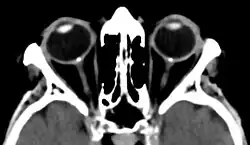

| Bilateral optic disc drusen in computed tomography seen as dense spots at the optical disc | |